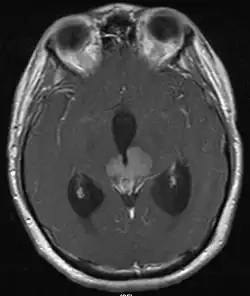

Le germinome pinéal est une forme rare de tumeur cérébrale, touchant principalement les adolescents de sexe masculin. Elle se caractérise par une lésion siégeant le plus souvent autour du troisième ventricule cérébral et touche souvent la glande pinéale elle-même, ainsi que le compartiment supra-sellaire. En fonction de la zone touchée, les symptômes peuvent comprendre l'hydrocéphalie, des troubles visuels (diplopie par exemple), acouphènes, et anomalies endocriniennes. Leur taux de survie à 10 ans est de plus de 90%[1]

Le diagnostic repose en premier lieu sur l'IRM du cerveau, puis le type histologique[8] de la tumeur est précisé par une biopsie stéréotaxique, réalisée par un neurochirurgien. On profite généralement de cette opération pour réaliser, en plus une ventriculocisternostomie[8], pour permettre l'écoulement du liquide cérébro-spinal, ou liquide céphalo-rachidien en ancienne nomenclature. Ce geste est essentiel pour réduire l'HTIC, qui demeure une urgence médico-chirurgicale.